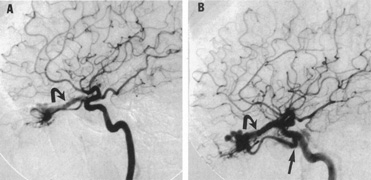

From 85% to 90% of AVMs are in the supratentorial compartment and are supplied primarily by the carotid circulation (Figs. 7 and 8). The remainder are supplied by the vertebrobasilar system. The approximate frequency of location is as follows: frontal, 22%; temporal, 18%; parietal, 27%; occipital, 5%; and deep intraventricular or paraventricular, 18%. The intracerebral site of the malformation does not necessarily indicate that there will be signs referable to that area simply from the mass effect of the malformation. Clinical features primarily result from subarachnoid hemorrhage or intraparenchymal hemorrhage with hematoma formation.

Fig. 7. Supratentorial arteriovenous malformation in a 28-year-old woman with a history of focal motor seizures for many years and a recent subarachnoid hemorrhage. A: Lateral projection carotid arteriogram demonstrating a huge deep hemispheral arteriovenous malformation. B: Frontal projection. C: Fundus photograph showing anomalous tortuous vasculature in each eye. No retinal arteriovenous shunt was detectable.

Fig. 8. Multiple supratentorial arteriovenous malformations (AVMs). A: Lateral projection of left carotid arteriogram shows dilated afferent artery (solid arrow) feeding the right hemispheric parietal AVM (open arrow). B: Right carotid injection fills a second, more posteriorly located, parietooccipital AVM (open arrow), which drains immediately to markedly dilated cortical veins (curved arrow).